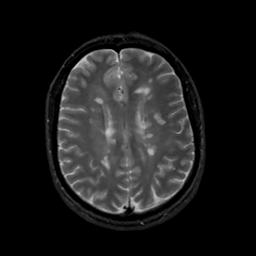

MR Study #16, June 23, 1991 -- Slice #33

[Home][Help][Clinical][Tour 1][Tour 2] Slice 33